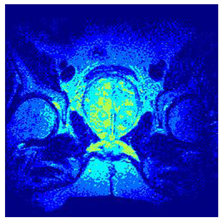

In this subsection, we will discuss the experiment designed to evaluate the performance of EO with cross-entropy for the segmentation of prostate MRI images. To this end, we use a group of reference images formed by a set of six prostate MRI images; see Figure 4. All the images from the group were extracted from the Ferenc Jolesz National Center for Image-Guided Therapy, Harvard Medical School, or Brigham Health Hospital datasets with no additional preprocessing [50]. Prostate MRI images are primarily used for disease diagnosis or to establish treatment for prostate-related diseases such as prostatitis, benign prostatic hyperplasia (BPH), and prostate cancer, among other diseases or medical conditions. In the context of this article, the images were used to test the efficiency of the equilibrium optimizing algorithm and compare it with the other six chosen algorithms. The segmentation of MRIs is carried out over four different thresholds levels: = 3, 4, 5, and 8. Due to the nature of the images, there was a limited number of different tissues in the images; thus, there was no point in evaluating a larger number of .

Figure 4.

Eleven transaxial-cut prostate MRI images. This figure presents a set of eleven transaxial-cut magnetic resonance (MR) images of the prostate. These images serve as the input dataset for evaluating the segmentation performance of the proposed algorithm.

Table 5 presents the segmentation of the MRIs using EO for a qualitative inspection. From Figure 5, it is clear that two lumps in the prostate have been highlighted by the thresholding process. Prostatic MRIs present noisy conditions, which makes it difficult to visualize the thresholding with the naked eye, so in Figure 5 we present the thresholded image as well as the histogram with the values of the thresholds generated by the EO. It can be observed in the histogram that the thresholds present an adequate distribution, even though this particular image has impulsive noise and a simple shape. Our findings indicate that four thresholds are typically sufficient for this application, which corresponds to identifying five different tissue types in the image. A smaller threshold value may result in a lack of sufficient contrast to highlight relevant anatomical structures, such as the prostate capsule. In contrast, a higher number of thresholds may lead to the incorrect differentiation of anatomical regions that should be connected.

Table 5.

Segmentation of transaxial-cut prostate MRI images Using EO and cross-entropy. This table presents the segmentation results of transaxial-cut prostate MRI images using the equilibrium optimizer (EO) and cross-entropy. Each row corresponds to a distinct MRI image, while the columns nt represent the number of thresholds applied during segmentation. The results illustrate the performance of the EO algorithm across different threshold levels for each image.